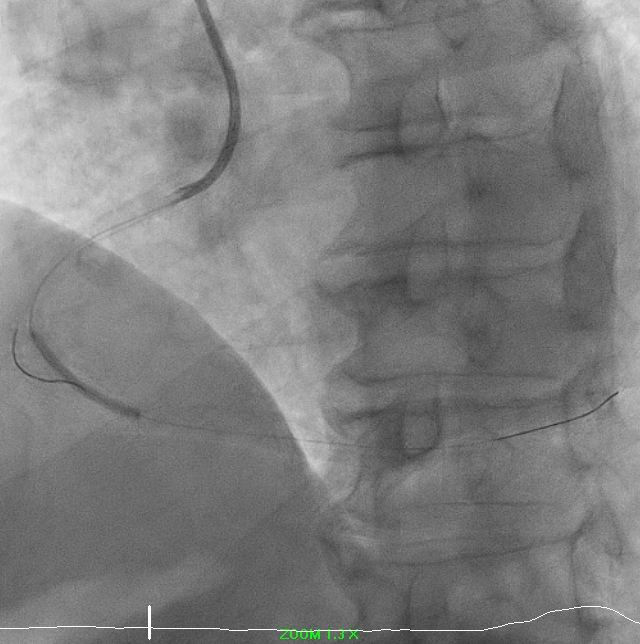

Predilation was challenging due to poor support. Initial 0.75 mm balloon could not pass; support was augmented with Sion Blue to RV branch. Subsequent predilation was performed sequentially with Zinrai 0.75 ¡¿ 4 mm, Ryureo 1.0 ¡¿ 5 mm, and NC balloon 2.0 ¡¿ 15 mm, achieving satisfactory antegrade flow. IVUS assessment demonstrated a distal vessel diameter of 2.5 mm, proximal/mid 3.5 mm, previous MSA 3.5 mm, and 360¡Æ proximal calcium. Additional predilation using Wedge 2.5 ¡¿ 15 mm (distal¡æproximal) and Scoreflex 3.0 ¡¿ 15 mm (mid¡æproximal) resulted in <30% recoil and no dissection. Post-IVUS, MSA improved from 3.5 ¡æ 4.8 mm.